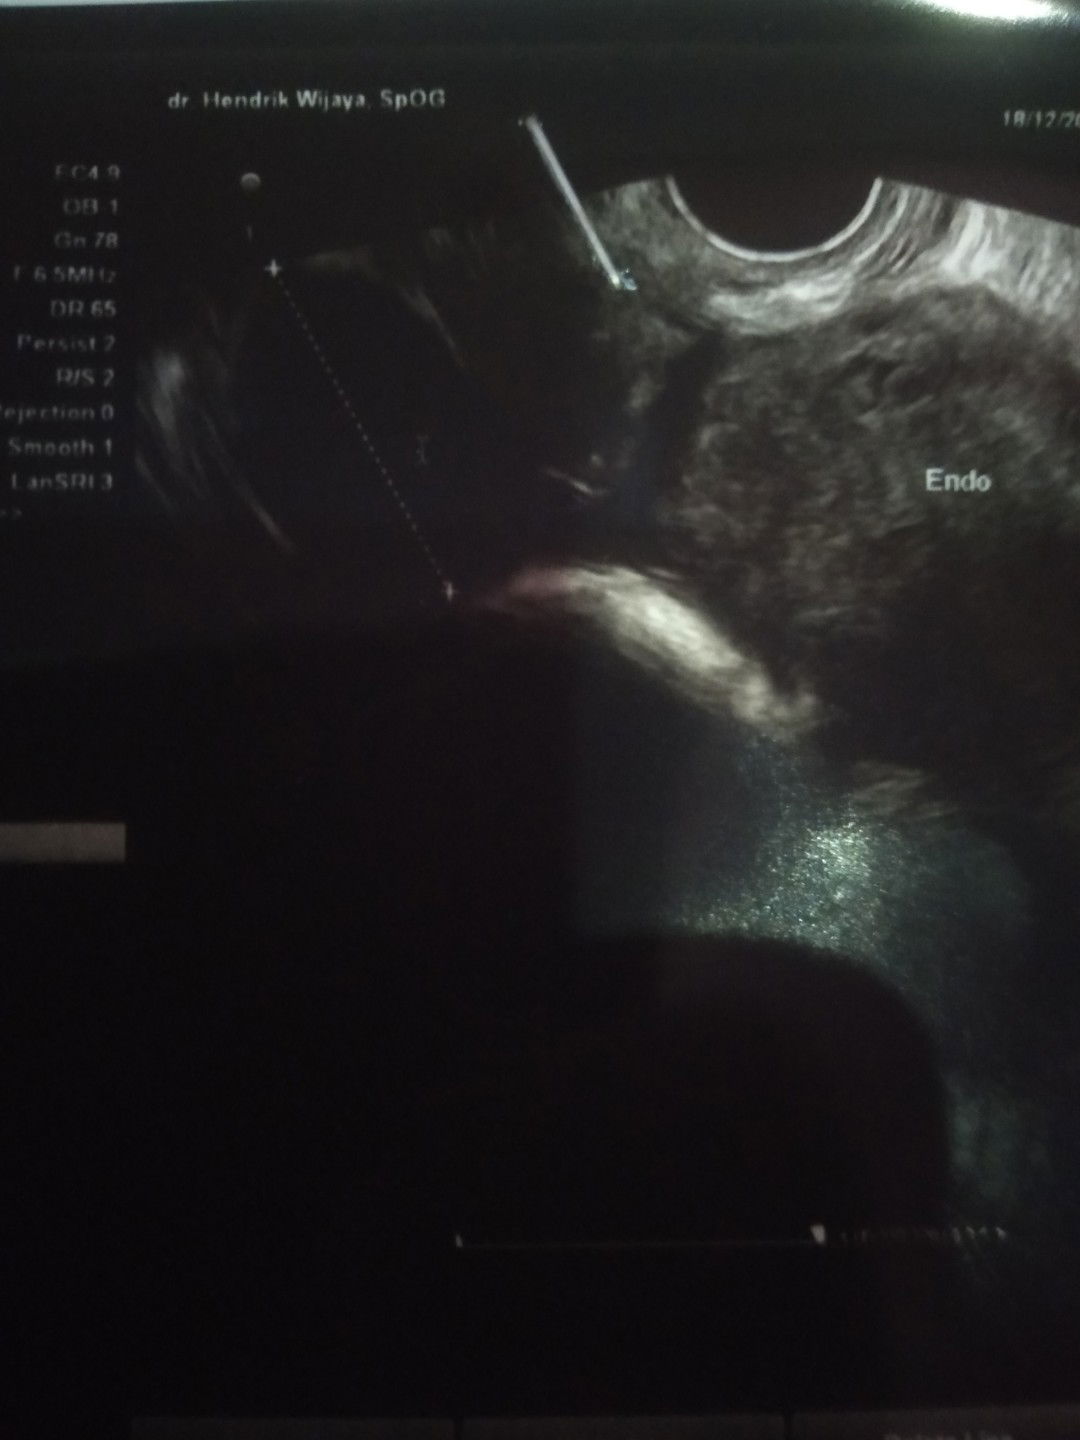

Saya mau tanya HPHT saya kan 18 nov..kemarin saya testpack positif .tp las saya usg..kan transvaginal..ktanya belum hamil..itu gimana ya